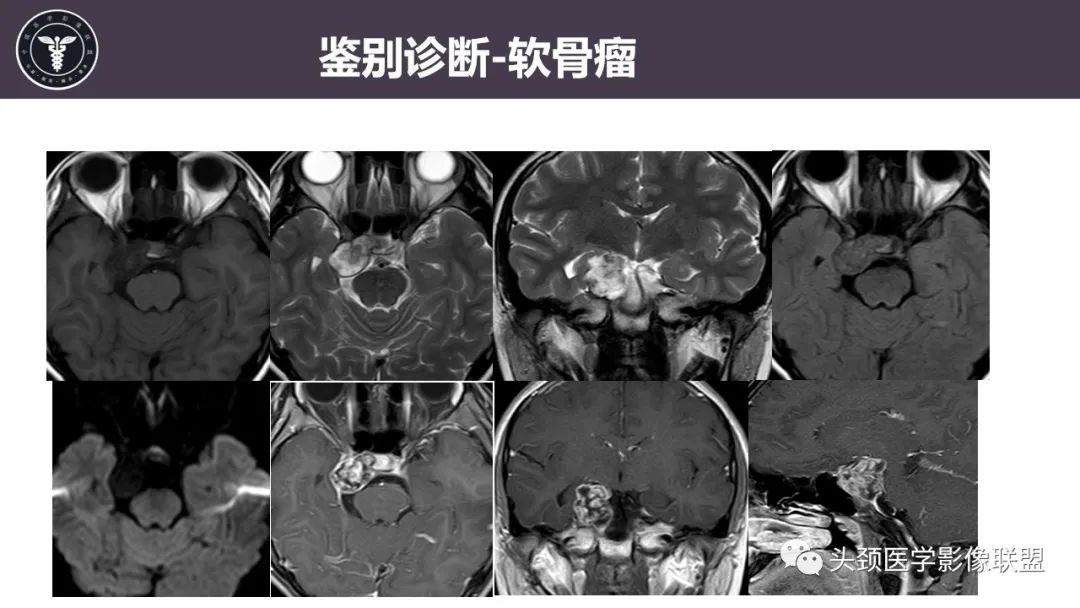

【病例】斜坡区骨巨细胞瘤 VS 脊索瘤-30

【病例】斜坡区骨巨细胞瘤 VS 脊索瘤-31